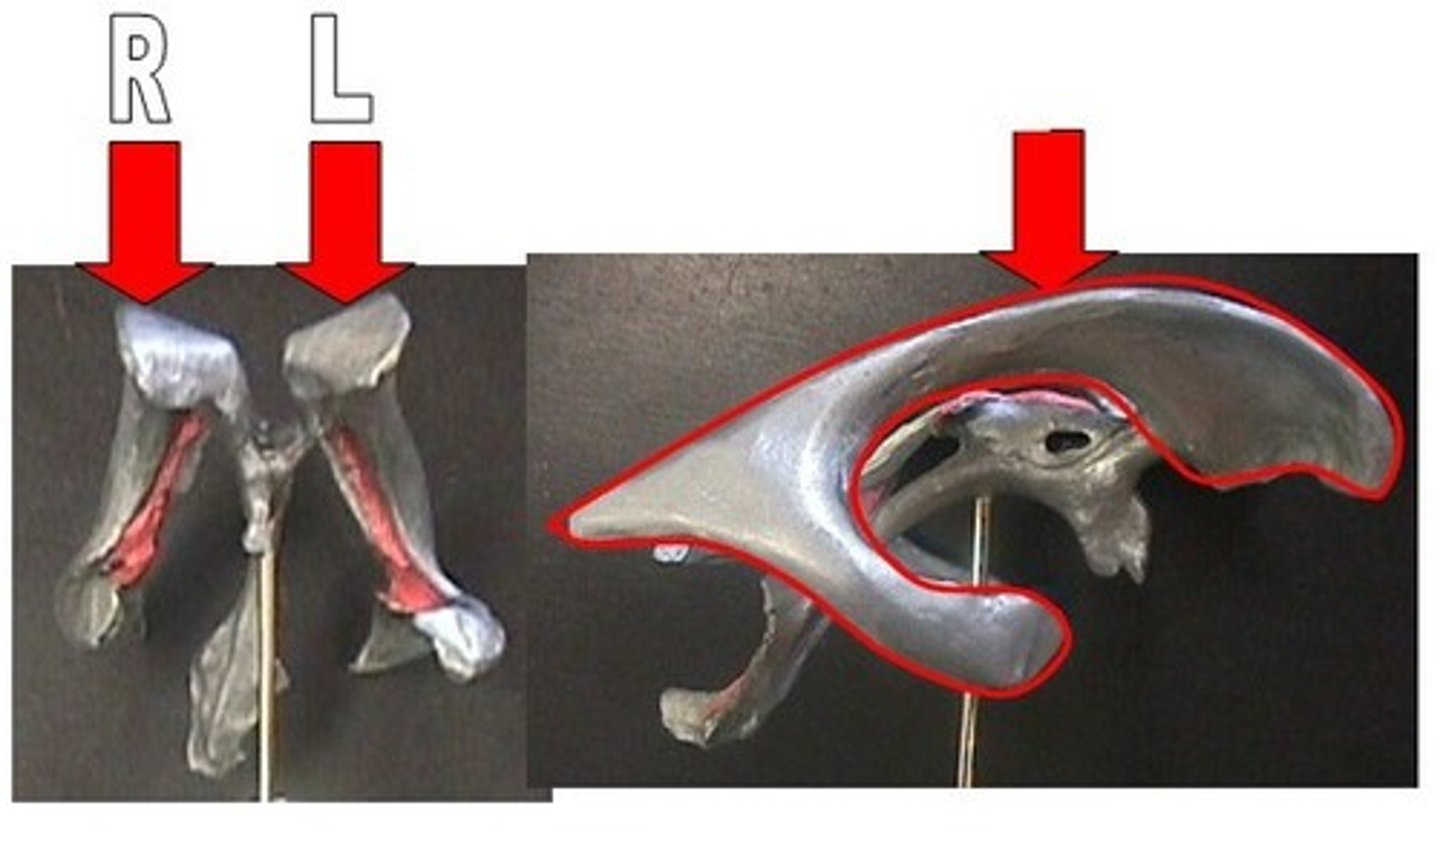

lateral ventricles